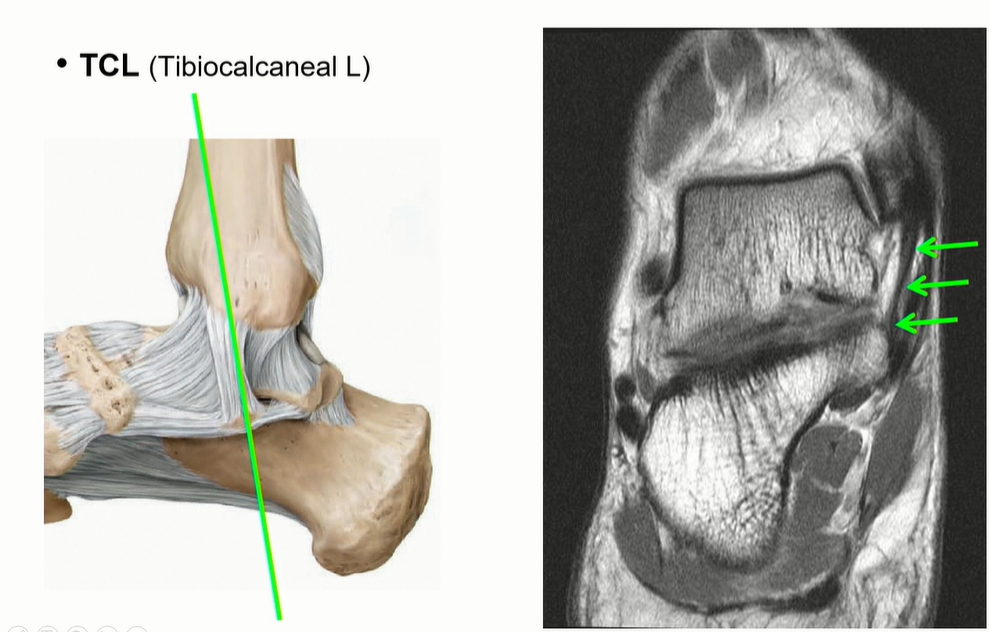

Tibiocalcaneal ligament는 calcaneus의 sustentaculum tali로 이어짐. 비교적 수직으로 주행하기 때문에 관찰 용이.

(Deltoid ligament의 superficial ligament의 3번에 해당)